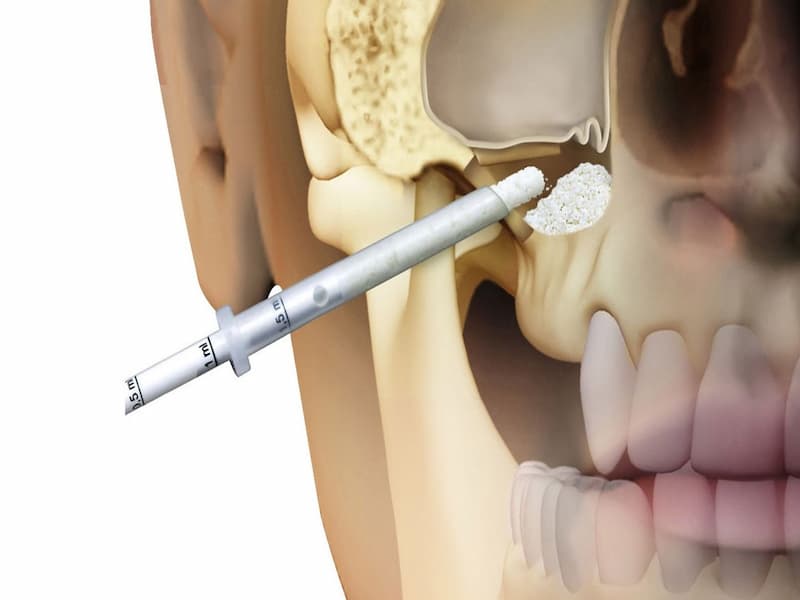

در واقع با استفاده از این روش می توان دندان مصنوعی قرار داد که معمولا با جراحی کردن نیز همراه است.

یکی از مهم ترین مشخصات و خصوصیات بارز ایمپلنت فوری فک پایین استحکام و ماندگاری بسیار بالای آن است.

تیتانیوم و زیرکونیا جنس اصلی پایه ایمپلنت می باشد که درجه کیفیت بسیار خوبی داشته و به هیچ عنوان دچار خرابی و شکستگی نمی شود.